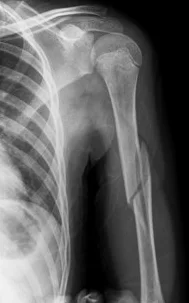

Humeral Shaft Fracture

- Possible associated injury to The Radial nerve (why?)(signs?)

Humeral Shaft Fracture- Management

- Conservative: U-shape slab) / splint / orthosis

- Gravity maintains reduction

- Management:

- Operative: (plate or IMN)